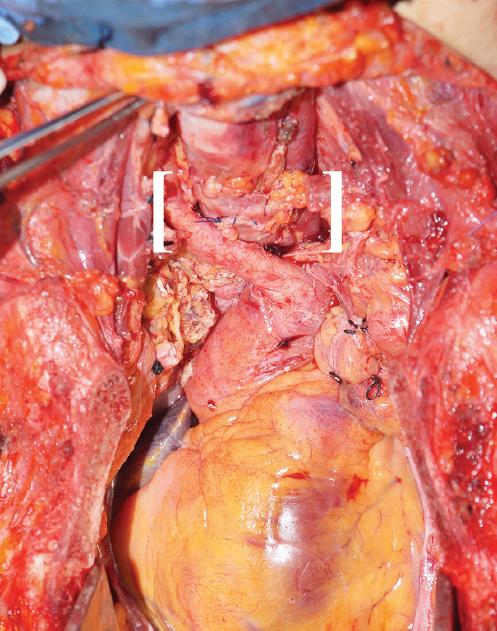

Se programa para traqueostomía y reconstrucción esofágica. Se inicia el abordaje cervical transversal 2 cm por encima de la escotadura yugular y esternotomía media con sierra automática. Se identifican la fístula traqueoesofágica (Fig. 3) y las estructuras vasculares, troncos supraaórticos y sistemas venosos. Se identifica el defecto esofágico (Fig. 4) en su porción cervical, de aproximadamente 4 cm de diámetro. Se procede a realizar cierre primario del defecto con sutura de Vicryl® 2-0 en un plano y posteriormente se coloca un parche muscular. Se procede a realizar traqueostomía en V, 5 cm por arriba de la carina, y se coloca una nueva cánula endotraqueal estéril (Fig. 5). Posteriormente se procede al desinflado del balón por parte del servicio de anestesiología, el retiro de la cánula orotraqueal con aspiración de secreciones y la reconexión al circuito de ventilación con la cánula endotraqueal previamente descrita. Se realizan resección traqueal y anastomosis terminoterminal con Prolene® 4-0 con puntos simples por fuera de la mucosa (Fig. 6). Se procede al cierre de la esternotomía con sutura de alambre con técnica hemi-Robicsek y al cierre de la cervicotomía por planos, previa colocación de drenaje. Lamentablemente, la paciente fallece en el posoperatorio inmediato debido a falla orgánica múltiple.

Figura 4 Imagen transoperatoria del defecto esofágico, por debajo del músculo constrictor de la faringe, con bordes revitalizados para permitir el cierre primario.